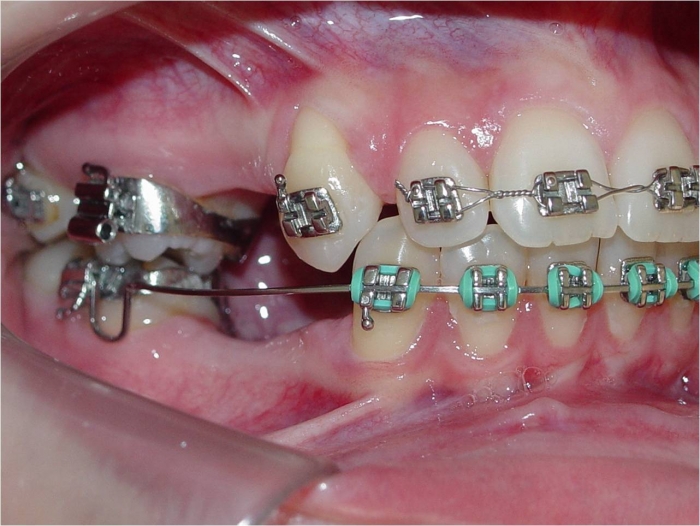

Imagem inicial

Dentes de porcelana instalados sobre implantes